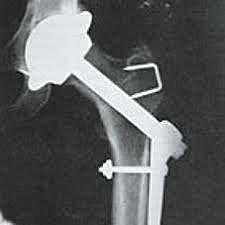

• Philip Wiles

Philip Wiles

implanto en una sustitución de cadera componentes emparentados de acetábulo y fémur a base de acero inoxidable

se estabiliza mediante tornillo y el componente de la cabeza mediante un tallo, placa lateral y tornillos.